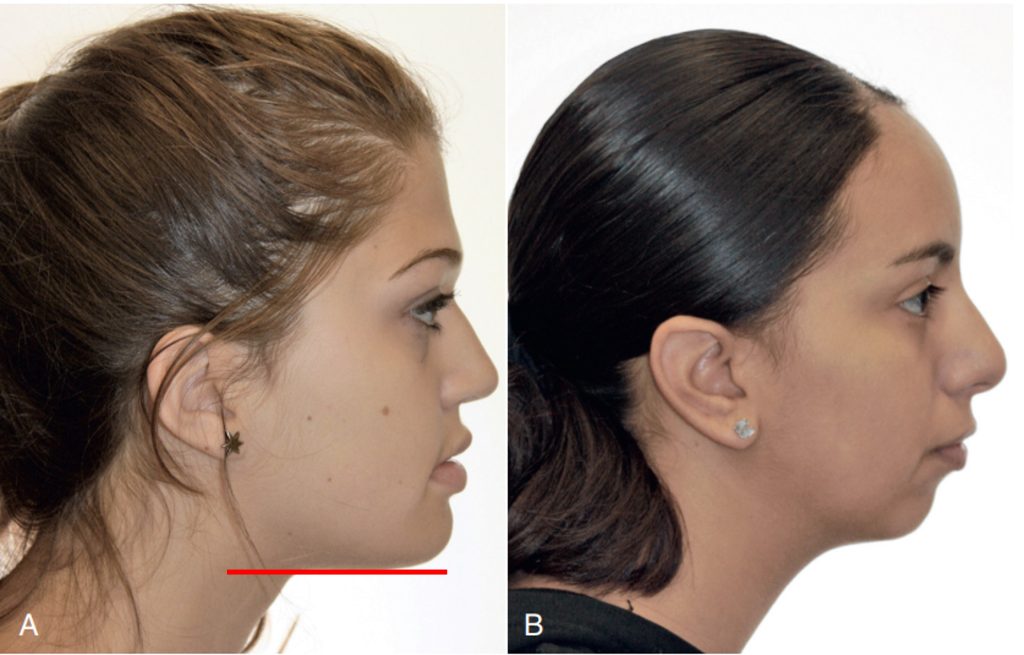

Thông thường, ba cấu trúc này duy trì một độ nhô (lồi) nhẹ, và độ nhô (lồi) này sẽ giảm đi trong tuổi dậy thì do sự phát triển không đồng đều của hai xương hàm. Trong giai đoạn bùng phát tăng trưởng dậy thì, hàm dưới có sự di chuyển ra trước nhiều hơn so với hàm trên. Cần lưu ý rằng khi kết thúc tăng trưởng, có sự khác biệt về giới tính trong độ nhô khuôn mặt, thường thì khuôn mặt nữ giới có xu hướng nhô hơn do xương cằm ít nhô ra hơn.

Thông thường, tương quan song song hoặc có góc âm nhẹ (điểm cổ họng nằm cao hơn điểm menton) được thấy ở những khuôn mặt có thẩm mỹ tốt (hình 1-27A). Cằm kém phát triển sẽ thể hiện qua sự giảm chiều dài từ cằm đến cổ họng (hình 1-27B).